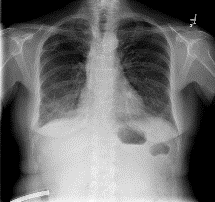

Among various medical imaging tools, chest radiographs are the most important and widely used diagnostic tool for detection of thoracic pathologies. Research is being carried out in order to propose robust automatic diagnostic tool for detection of pathologies from chest radiographs. Artificial Intelligence techniques especially deep learning methodologies have found to be giving promising results in automating the field of medicine. Lot of research has been done for automatic and fast detection of pneumothorax from chest radiographs while proposing several frameworks based on artificial intelligence and machine learning techniques. This study summarizes the existing literature for the automatic detection of pneumothorax from chest x-rays along with describing the available chest radiographs datasets. The comparative analysis of the literature is also provided in terms of goodness. Limitations of the existing literature along with the research gaps is also given for further investigation. The paper provides a brief overview of the present work for pneumothorax detection for helping the researchers in selection of optimal approach for future research.